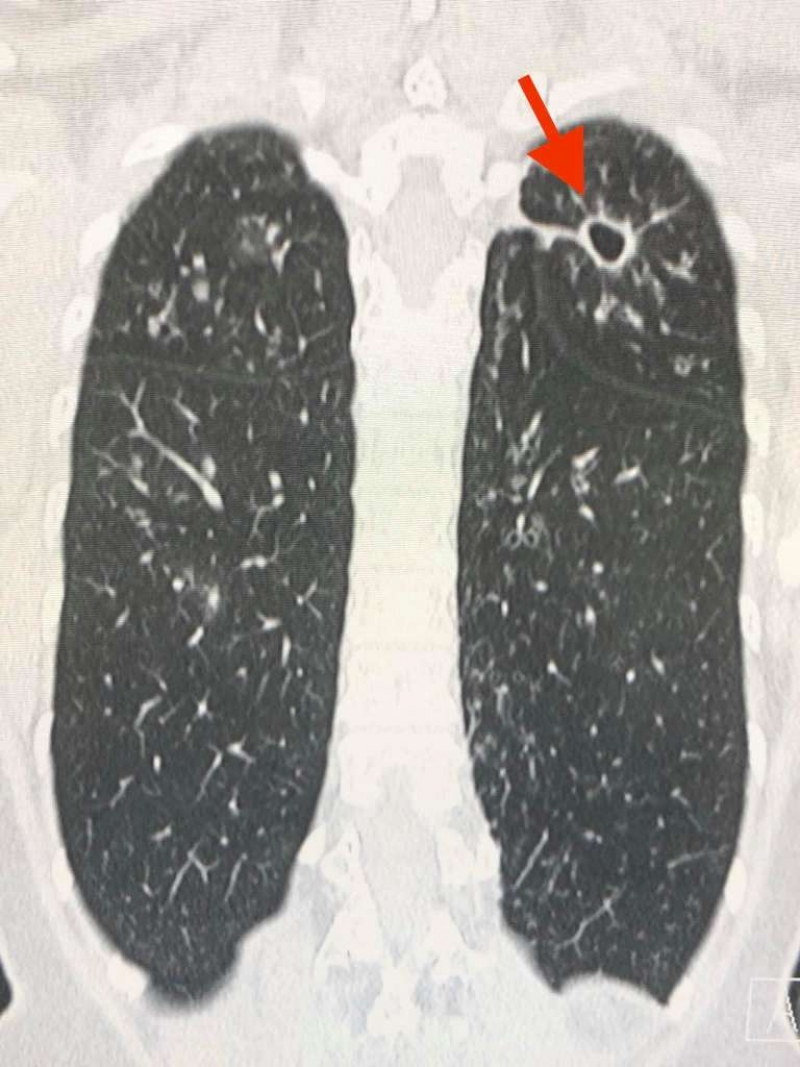

สาเหตุที่สำคัญน่าจะเป็นจากเชื้อไวรัสโควิด-19 ในประเทศอิตาลีเป็นเชื้อสายพันธุ์ที่ดุร้ายกว่าประเทศอื่นในเอเชีย สามารถเพิ่มจำนวนในปอดได้รวดเร็ว ทำให้แพร่กระจายเชื้อให้ผู้อื่นมากขึ้น และเชื้อนี้เล่นงานปอดอย่างหนัก ทำให้ปอดอักเสบอย่างรุนแรง ระบบหายใจล้มเหลว อัตราการเสียชีวิตจึงสูงมาก

ประเทศไทยกำลังมีเชื้อโควิดที่ดุร้ายจากประเทศอิตาลีแพร่ระบาด ยอดผู้ป่วยติดเชื้อรายใหม่ ดูรูป และผู้เสียชีวิตจากปอดอักเสบกำลังจะเพิ่มขึ้นอย่างรวดเร็ว สำหรับผู้ป่วยที่ติดเชื้อโควิดรายใหม่ที่เกี่ยวข้องกับสนามมวย แพทย์คงต้องให้ยาต้านไวรัสตัวใหม่จากประเทศญี่ปุ่น ชื่อยา Avigan คือฟาวิพิราเวียร์ Favipiravir และยาอื่นๆเช่น hydroxychloroquine เพราะผู้ป่วยรายใหม่กลุ่มนี้จะมีปอดอักเสบมากขึ้น ถ้าไม่ให้ มีโอกาสปอดล้มเหลวสูง